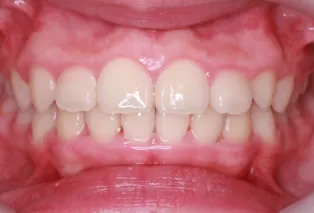

Intraoral photos